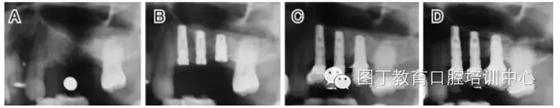

病例5 多顆種植體(圖7)

圖7